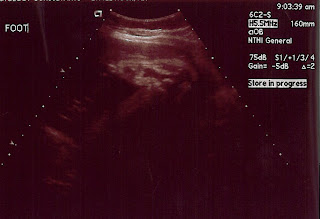

Let me tell you- those nurses were in NO hurry to get me checked out! Good thing I wasn't in horrific pain or anything! I was taken back to triage and was hooked up to the fetal monitors. One monitor for Ryan's heartbeat and one for the contractions. Nurse left me on the monitor for 2 hours. So, Matt and I just sat in the cold room watching tv for 2 hours waiting! My doctor came to check on me and that made me feel a lot better- she's so amazing! After the 2 hours were up, it was determined that I was having contractions but they were anywhere from 6-11 minutes apart and I wasn't progressing. So, my doctor sent us home in hopes that I'll make it to next Thursday so I can just be induced already!!